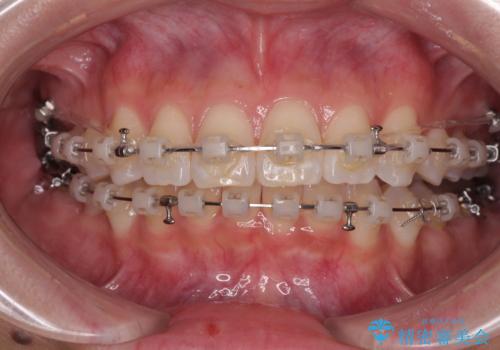

- 審美装置

- 2年2ヶ月

- 上下前歯のデコボコとディープバイトを気にして来院された患者様です。

歯列全体に叢生があり、舌の突出癖が認められたため、突出癖が改善されない場合には口元が突出するリスクが考えられました。

マウスピースでもワイヤーでも対応可能でしたが、煩わしいことは避けたいとのことで、舌のトレーニングをしっかりと行っていただきながら、ワイヤー装置にて矯正治療を行うこととしました。